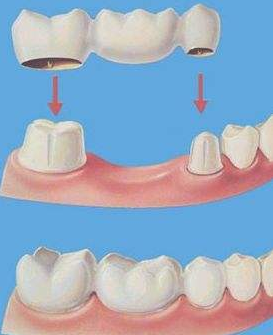

1、镶烤瓷牙:烤瓷牙适合牙齿缺失较少的老年人,而且要求旁边的牙齿是稳固的,因为烤瓷牙是需要把两边的牙齿磨小,然后镶上一个烤瓷牙冠就可以了。

对于门牙缺失来说,一般建议考虑种植牙或者烤瓷连桥修复,这个具体情况要实际检查后才能判断,详情可直接在线客服。